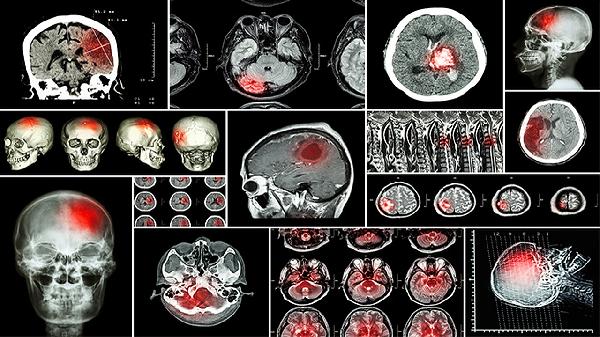

3、动脉硬化性头晕

适用于脑动脉硬化导致的反复发作性眩晕,尤其对伴随头部沉重感、步履不稳的症状效果明显。此类头晕多在体位改变时加重,可能与高脂血症、糖尿病等基础病相关。用药时可配合血塞通软胶囊改善脑循环,但急性脑血管意外患者禁用。饮食需控制动物内脏等高胆固醇食物摄入。

5、中风后遗症康复期

用于脑梗塞或脑出血恢复期的烦躁不安、语言不利等后遗症状辅助治疗。这类患者多见肢体麻木僵硬伴随情绪抑郁,通常与脑组织缺血缺氧有关。康复期用药需配合脑心通胶囊、银杏叶片等活血化瘀药物,但新发脑梗急性期禁用。康复训练应遵循循序渐进原则,避免过度疲劳。